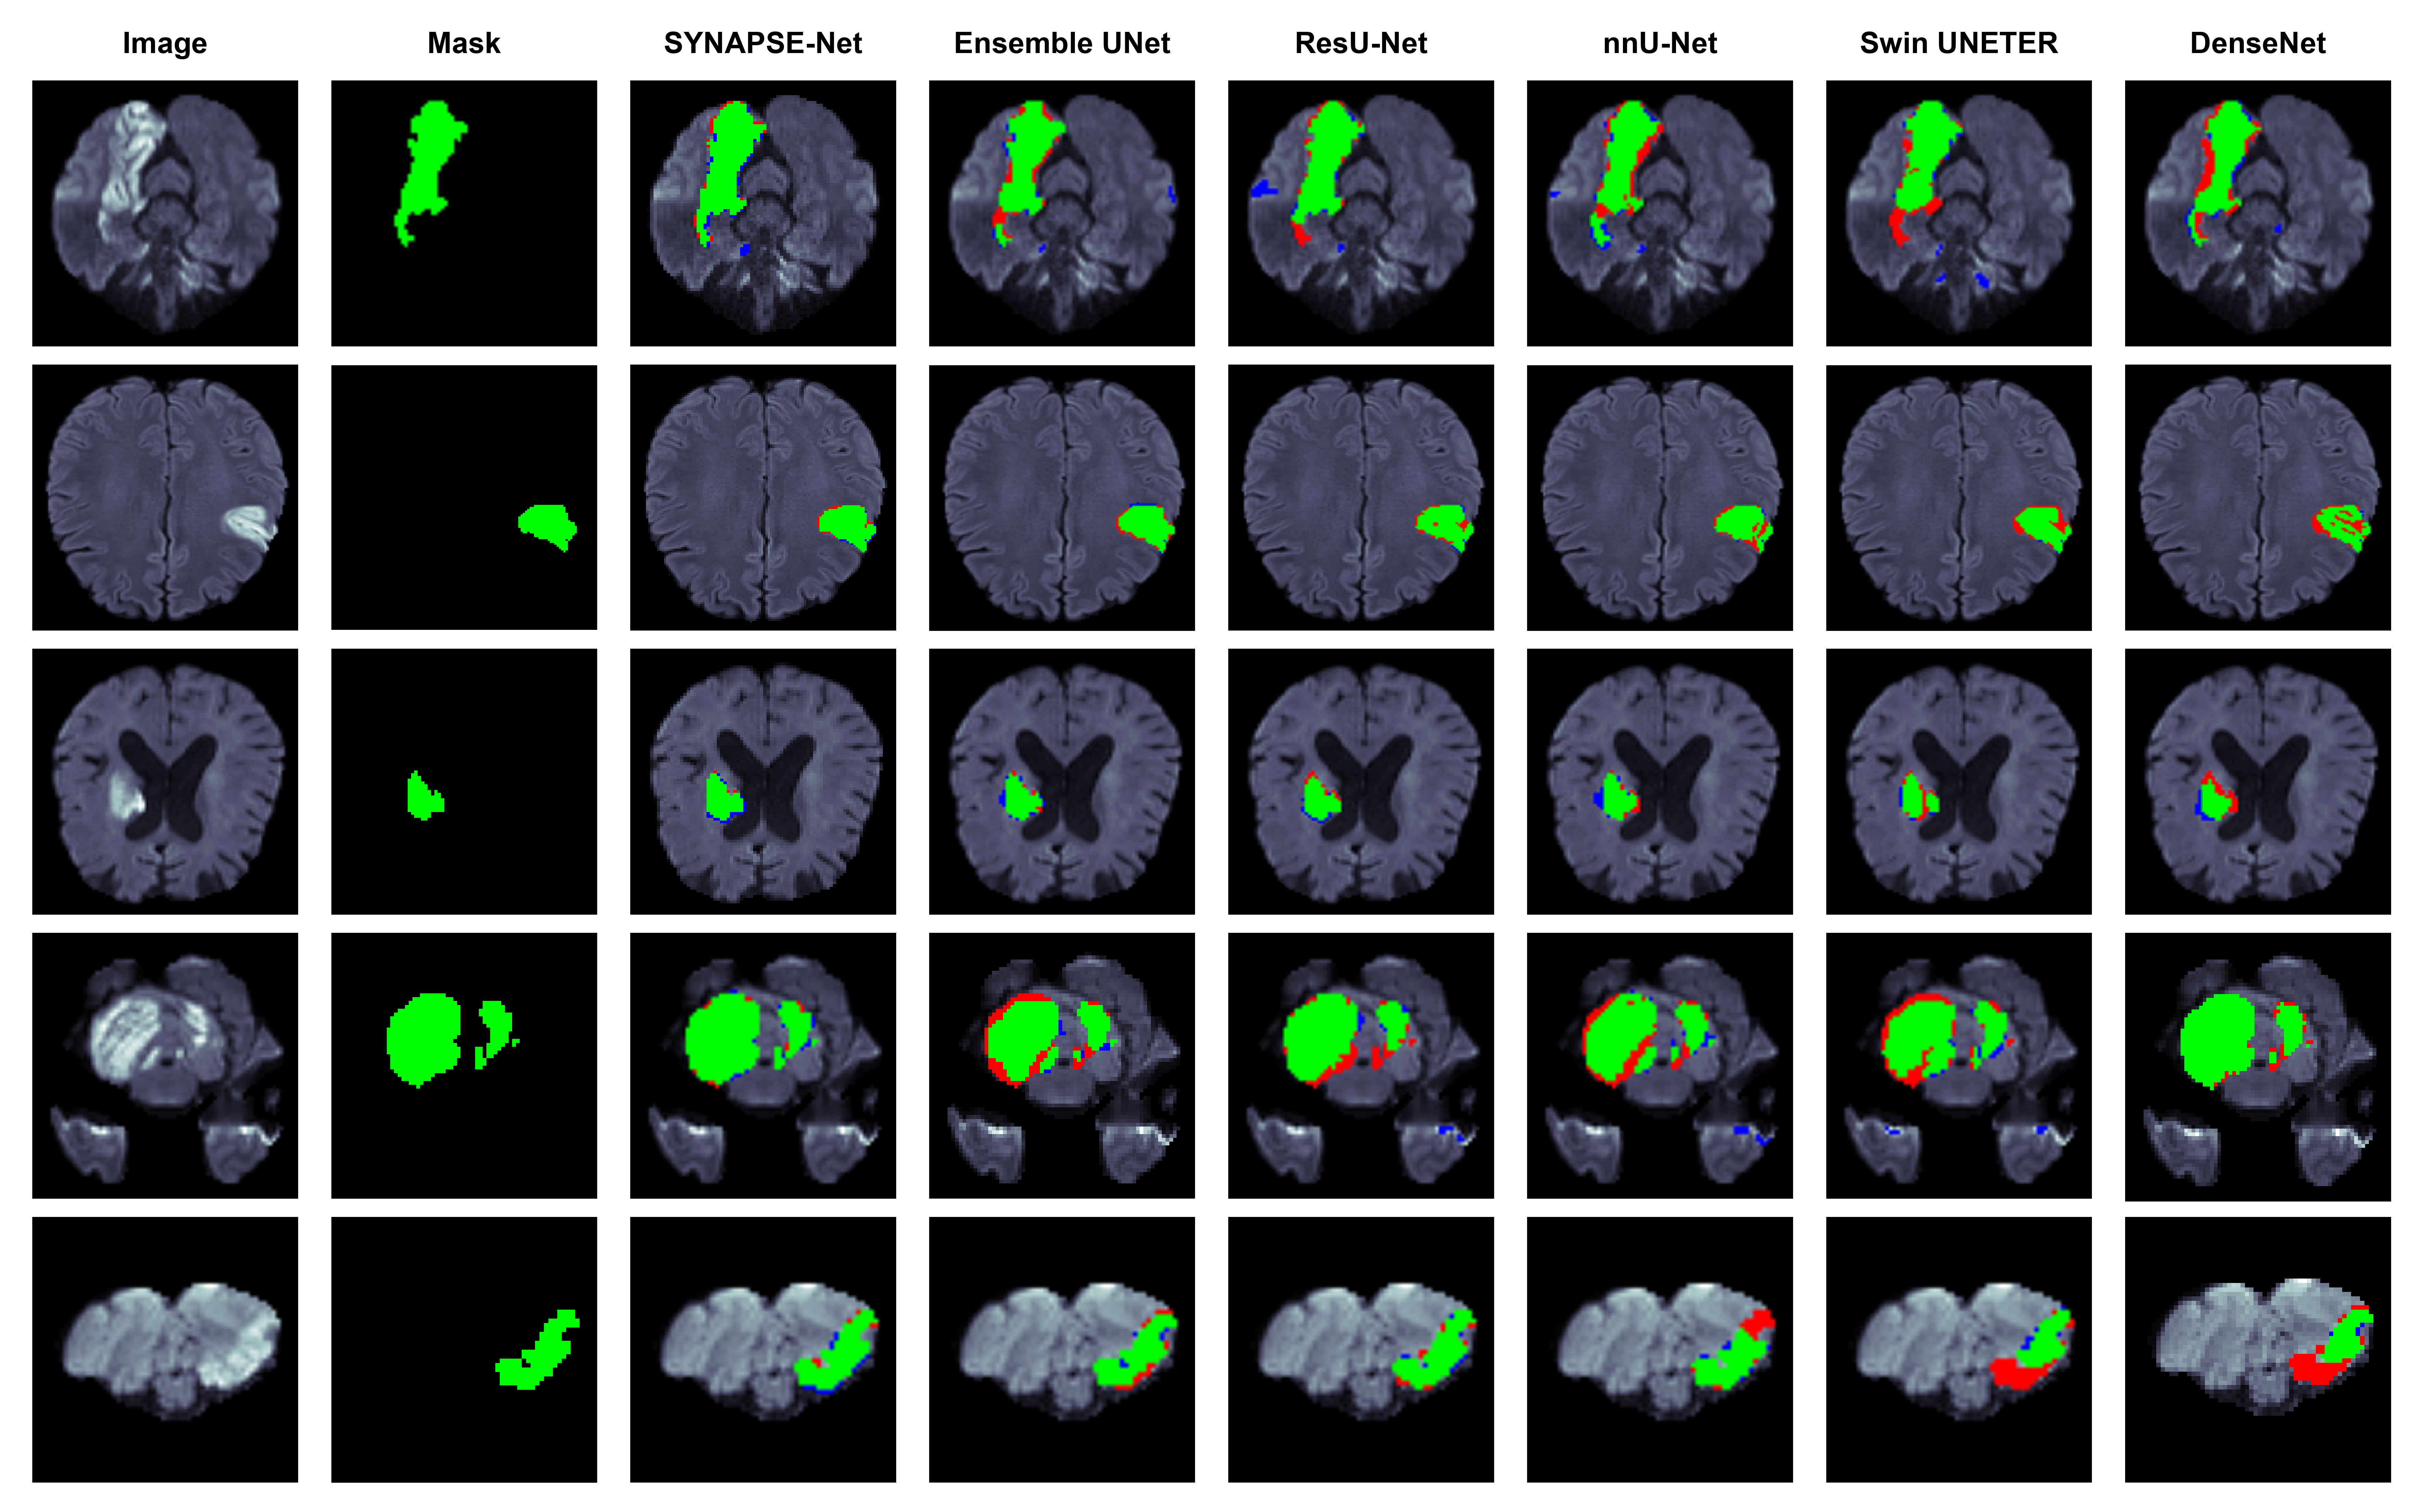

The next study evaluated the effects of our novel architectural components, using the complete training pipeline on each model. The quantitative findings are shown in Table 4 and qualitative examples provided in Fig. 5.

Refer to caption

Figure 5: Qualitative results of the architectural ablation study on the WMH dataset. Segmentation overlays show true positives (green), false negatives (red), and false positives (blue).

Our baseline (1), a standard UNet++, had a satisfactory DSC, but its large HD95 value and its instability clearly reflect its weaknesses in precision. The qualitative results in Fig. 5 are typical where the baseline model detects larger lesions but has noisy poorly defined borders and severe under-segmentation, especially for small lesions. Next, we evaluated the influence of our (2) advanced bottleneck that incorporates the multi-stream encoders, Swin Transformers, and the CMAF module. This addition resulted in a substantial boost in performance in a way that the mean DSC and the HD95 improved significantly. The reason for this improvement lies in the ability of the Swin Transformer in characteristic modeling of long-range spatial context as well as the intelligent multi-modal fusion capability of the CMAF module. Finally, the (3) full SYNAPSE-Net was assessed, which integrated our novel hierarchical gated decoder. The highest improvement was again noted in the HD95 measure, reducing by around 40%. This provides conclusive proof that hierarchical gating mechanism plays a significant role in achieving excellent geometric fidelity. By implementing high-level semantic features as a means of modulating the passage of low-level spatial information, the decoder defines intricate lesion borders more accurately. This finding is evident visually in Fig. 5, where the full model produces the finest boundaries with an ability to detect small subtle lesions missed by preceding frameworks. Additionally, as evident from the boxplots in Fig. 6, the standard deviation of all metrics reached their lowest points, demonstrating that the complete architecture is the most robust and reliable.

Figure 7: Qualitative comparison on the WMH test set. Green (True Positive), Red (False Negative/Missed Lesion), Blue (False Positive/Over-segmentation).

It is visual in rows of small lesions (row 1 and 4 of Fig. 7), where our system identifies almost all the small satellite lesions, in contrast to those of competing methods like Ensemble HFU-Net and FCN Ensembles. Such detection robustness as well as higher boundary detection competency in Table 6 validate our method’s performance for WMH segmentation.